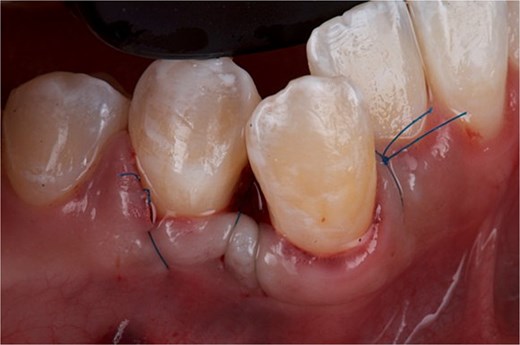

The surgical intervention was aimed at completely removing the hyperplastic lesion, with the objective of obtaining a definitive diagnosis through histopathological analysis and, simultaneously, eliminating the pathological tissue. Under aseptic and antiseptic conditions, local anesthesia was administered with 4% articaine with epinephrine 1:100 000. Subsequently, using a 15c scalpel blade, the base of the hyperplastic tissue was resected up to the interproximal area of teeth 43 and 44, ensuring adequate margins to guarantee complete removal of the lesion. Bone carving was then performed with a Kirkland periodontal chisel. The removed tissue was placed in 10% formalin and sent for histopathological study. To promote edge approximation and achieve primary healing, sharp dissection was performed, the flap was elevated to the mesial part of OD 43, and the wound was sutured with 5–0 nylon using simple stitches and a suspension stitch (Fig. 6). Antibiotic therapy (amoxicillin 750 mg every 12 hours for 7 days), analgesic (ibuprofen 600 mg every 8 hours for pain) and rinses with 0.12% chlorhexidine for 15 days were indicated.

Front view of the clinical image of the removal of the intraoral lesion with simple 5-point nylon suture and suspension stitches.